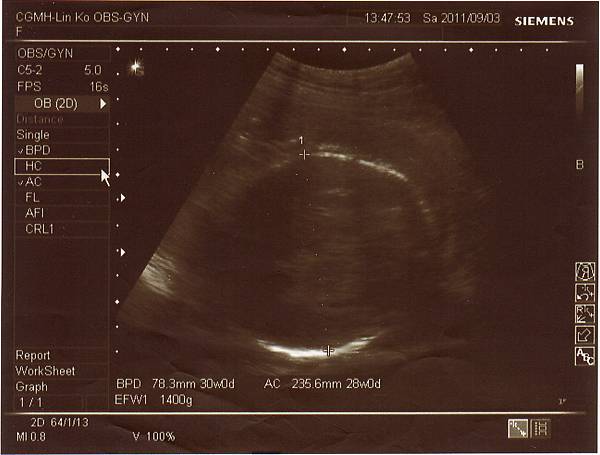

2011.09.03 兔寶妹已經三十週囉!

不僅胎位已經正了(醫生還說姿勢一百),體重也很正常來到1400公克,

連醫生都說看起來肚子不大但孩子卻長得很好呢!